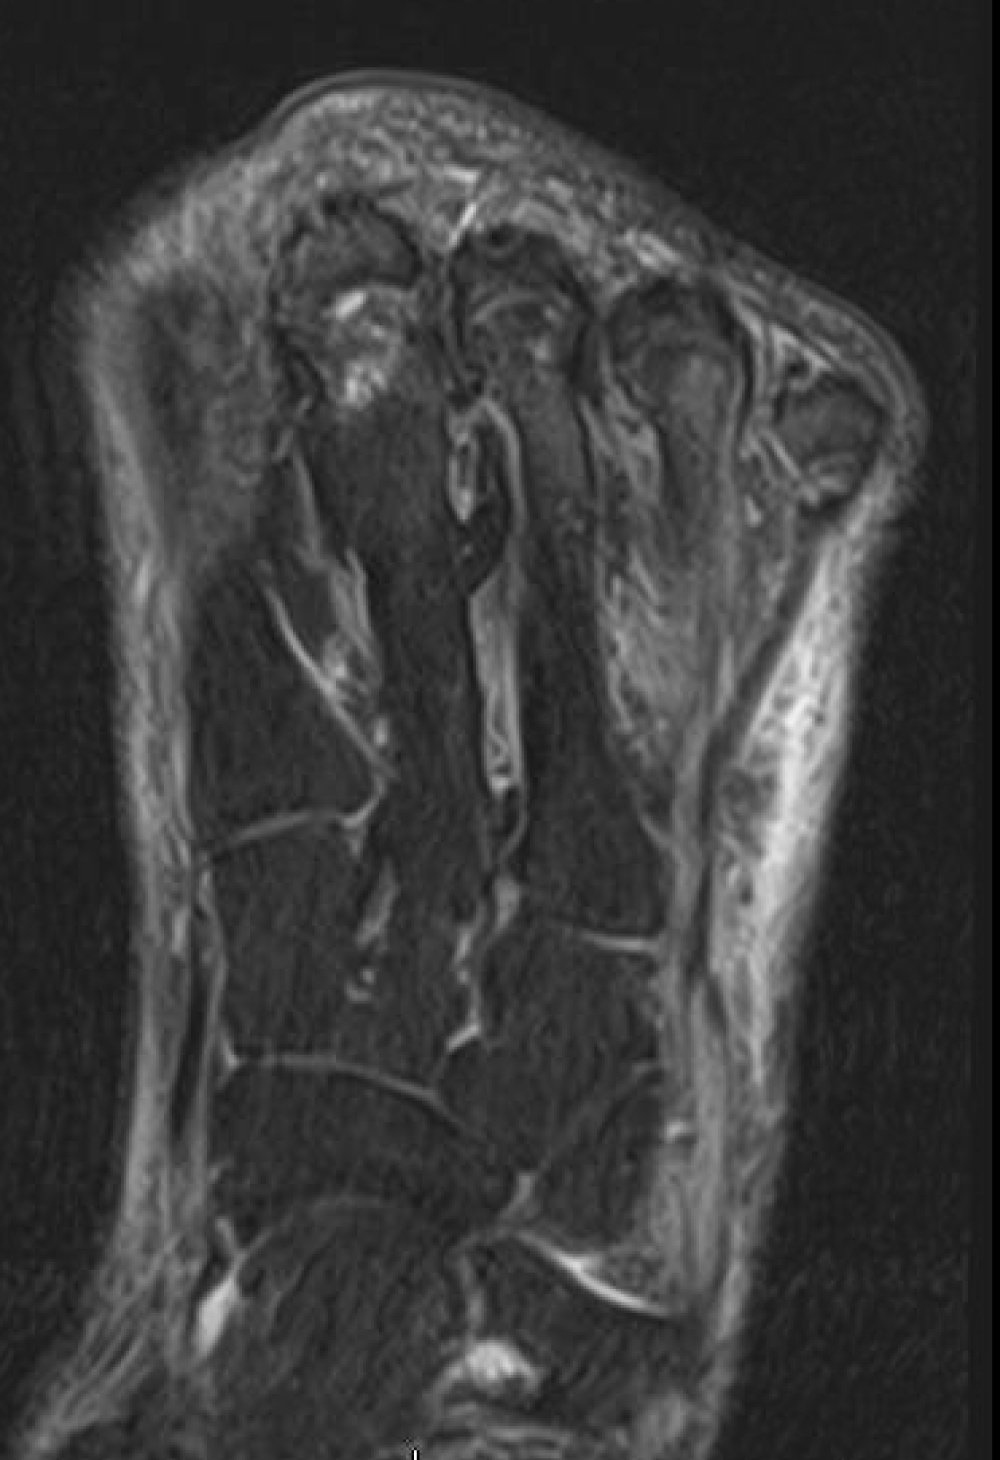

Radiograph were negative for gas gangrene, however, was suggestive for osteomyelitis of the second toe. The patient underwent an open guillotine amputation at the interphalangeal joint (Figure 2). An MRI of the forefoot post operatively showed that the metatarsals were unlikely to be infected with osteomyelitis thus no need for further resection (Figure 3). Prior to the final procedure, an in-depth discussion was had with the patient regarding amputation of all remaining toes. It was advised to the patient, leaving the lateral three toes would leave the patient at risk of developing new ulcerations which could become infected. It was recommended to the patient to undergo amputation of the remaining toes and a tendoachilles lengthening (TAL). A standard fish mouth incision pan-digital amputation, with a prophylactic tendoachilles lengthening was performed (Figure 4). The patient's post-operative recovery was uneventful and healed without complication. The patient was ambulating with little difficulty without a prosthetic in sneakers at the most recent clinic visit (Figure 5).

Figure 3: T-2 weighted magnetic resonance imaging (MRI) demonstrating minimal bone marrow edema of the metatarsal heads with no indication of osteomyelitis. View Figure 3